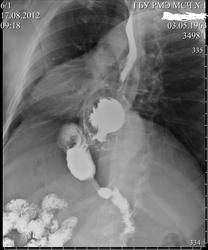

Пациент 49л.плотного телосложения, во время колки дров на даче, почувствовал резкие давящие боли в эпигастрии и в нижней части загрудинной области. Через 20 минут после приёма рюмки коньяка резкая боль отпустила, но полностью не прошла.Через несколько деней пришёл на R-скопию желудка с указанными жалобами.

Ну, аневризмы аорты точно нет ( хотя согласен, без полипозиционного исследования, можно в первую очередь об этом можно подумать) . Есть фиксированная грыжа пищеводного отверстия диафрагмы. Вопрос в том, что входит в грыжевой мешок кроме желудка?( дополнительную тень видно на всех снимках).

Пищевод не укорочен, огибает грыжевое выпячивание. Думаю, что параэзофагеальная грыжа. Хотя, по-мнению наших хирургов, это не существенно. Ход операции при грыжах один. А, что входит в грыжевой мешок??? Наверное желудок и входит, его кардиальная и субкардиальная части, дно и ,наверное, часть тела.

Добавлена боковая проекция.

Грыжа пищеводного отверстия диафрагмы. Контраст перед входом в желудок слегка задерживаться должен был. Не понимаю в чем вопрос, вроде так и выглядит обычно.